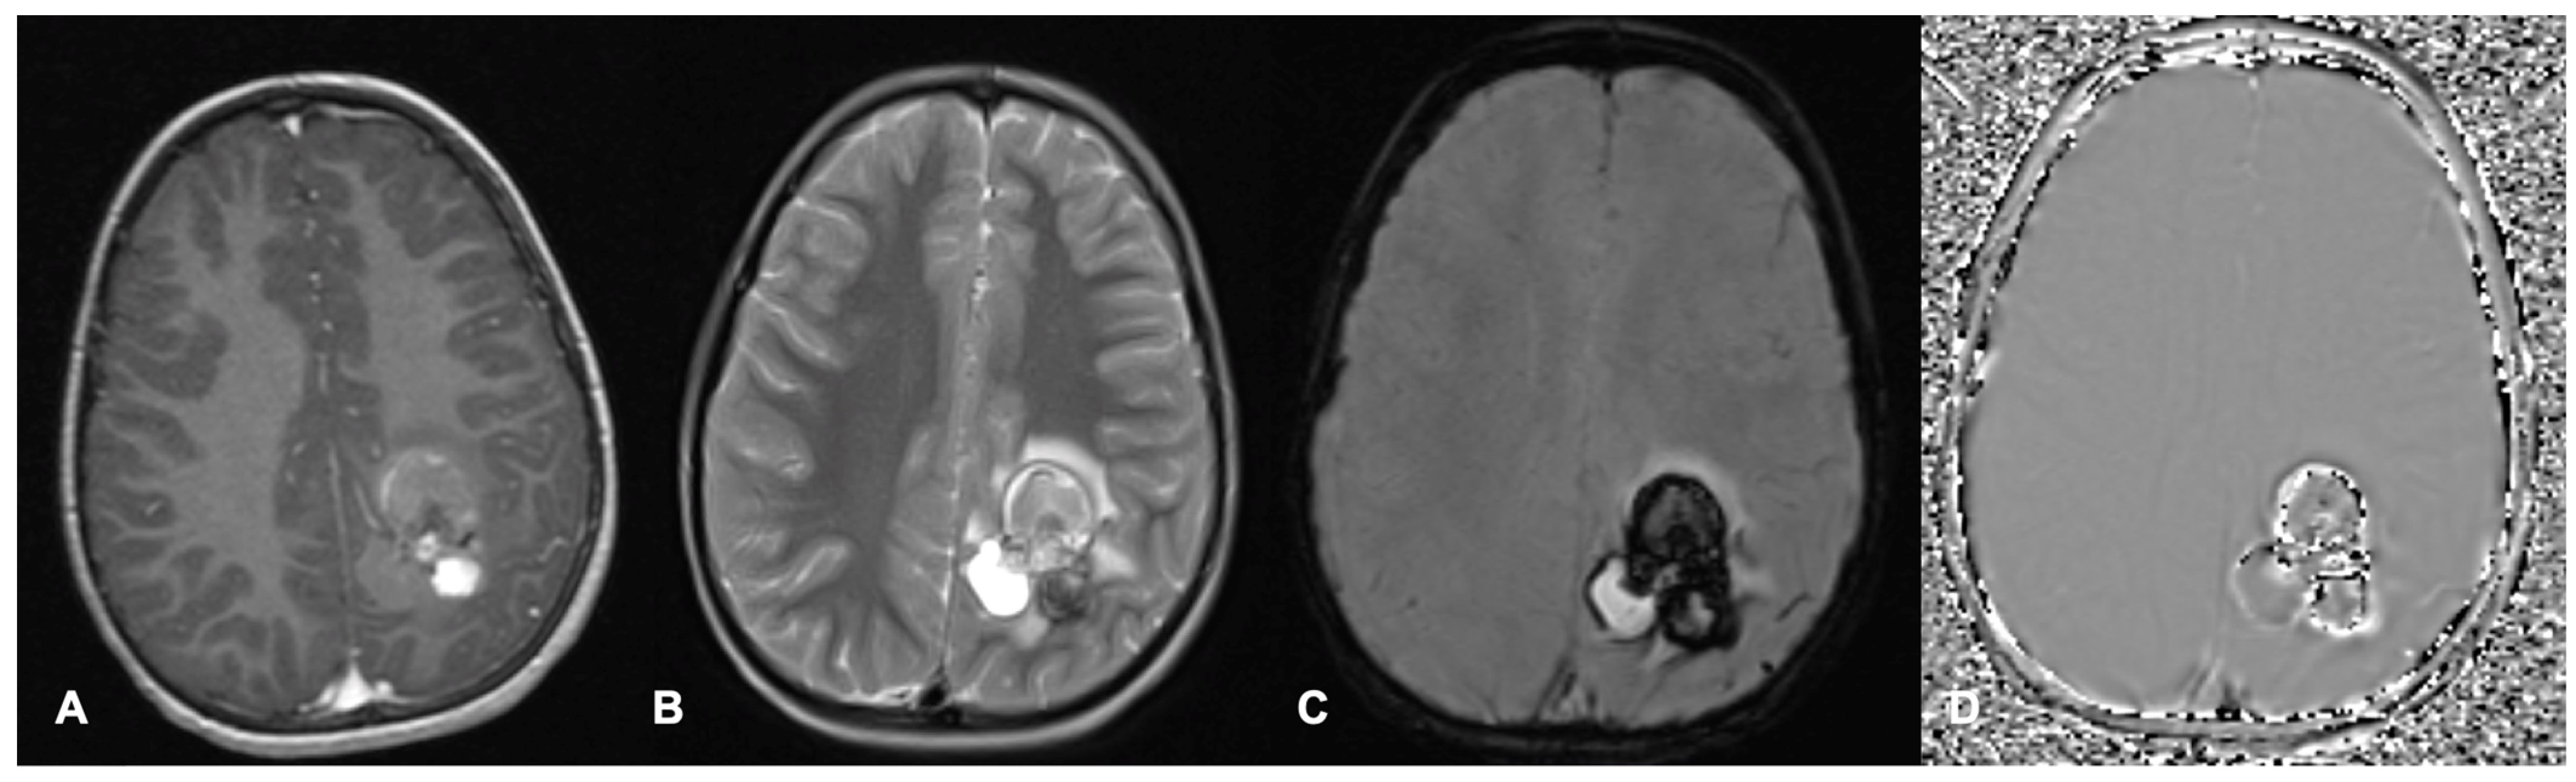

- Miller, N.G.; Reddick, W.E.; Kocak, M.; Glass, J.O.; Löbel, U.; Morris, B.; Gajjar, A.; Patay, Z. Cerebellocerebral diaschisis is the likely mechanism of postsurgical posterior fossa syndrome in pediatric patients with midline cerebellar tumors. AJNR Am. J. Neuroradiol. 2010, 31, 288–294. [Google Scholar] [CrossRef] [PubMed]